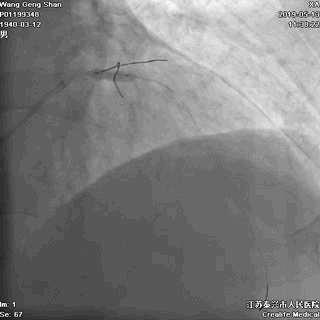

01 导丝进前三叉分支

对角支导丝到位

左冠共计5根导丝